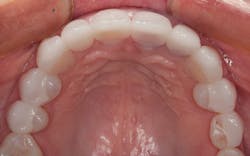

The final result can be seen from the occlusal view in Figure 9 and the retracted facial view in Figure 10. The patient’s new smile can be seen in Figure 11. Utilizing IPS e.max crowns and veneers, we were able to enhance the patient’s smile by creating a lighter color and a wider, more attractive look.

Figure 9: Occlusal view of the final restoration